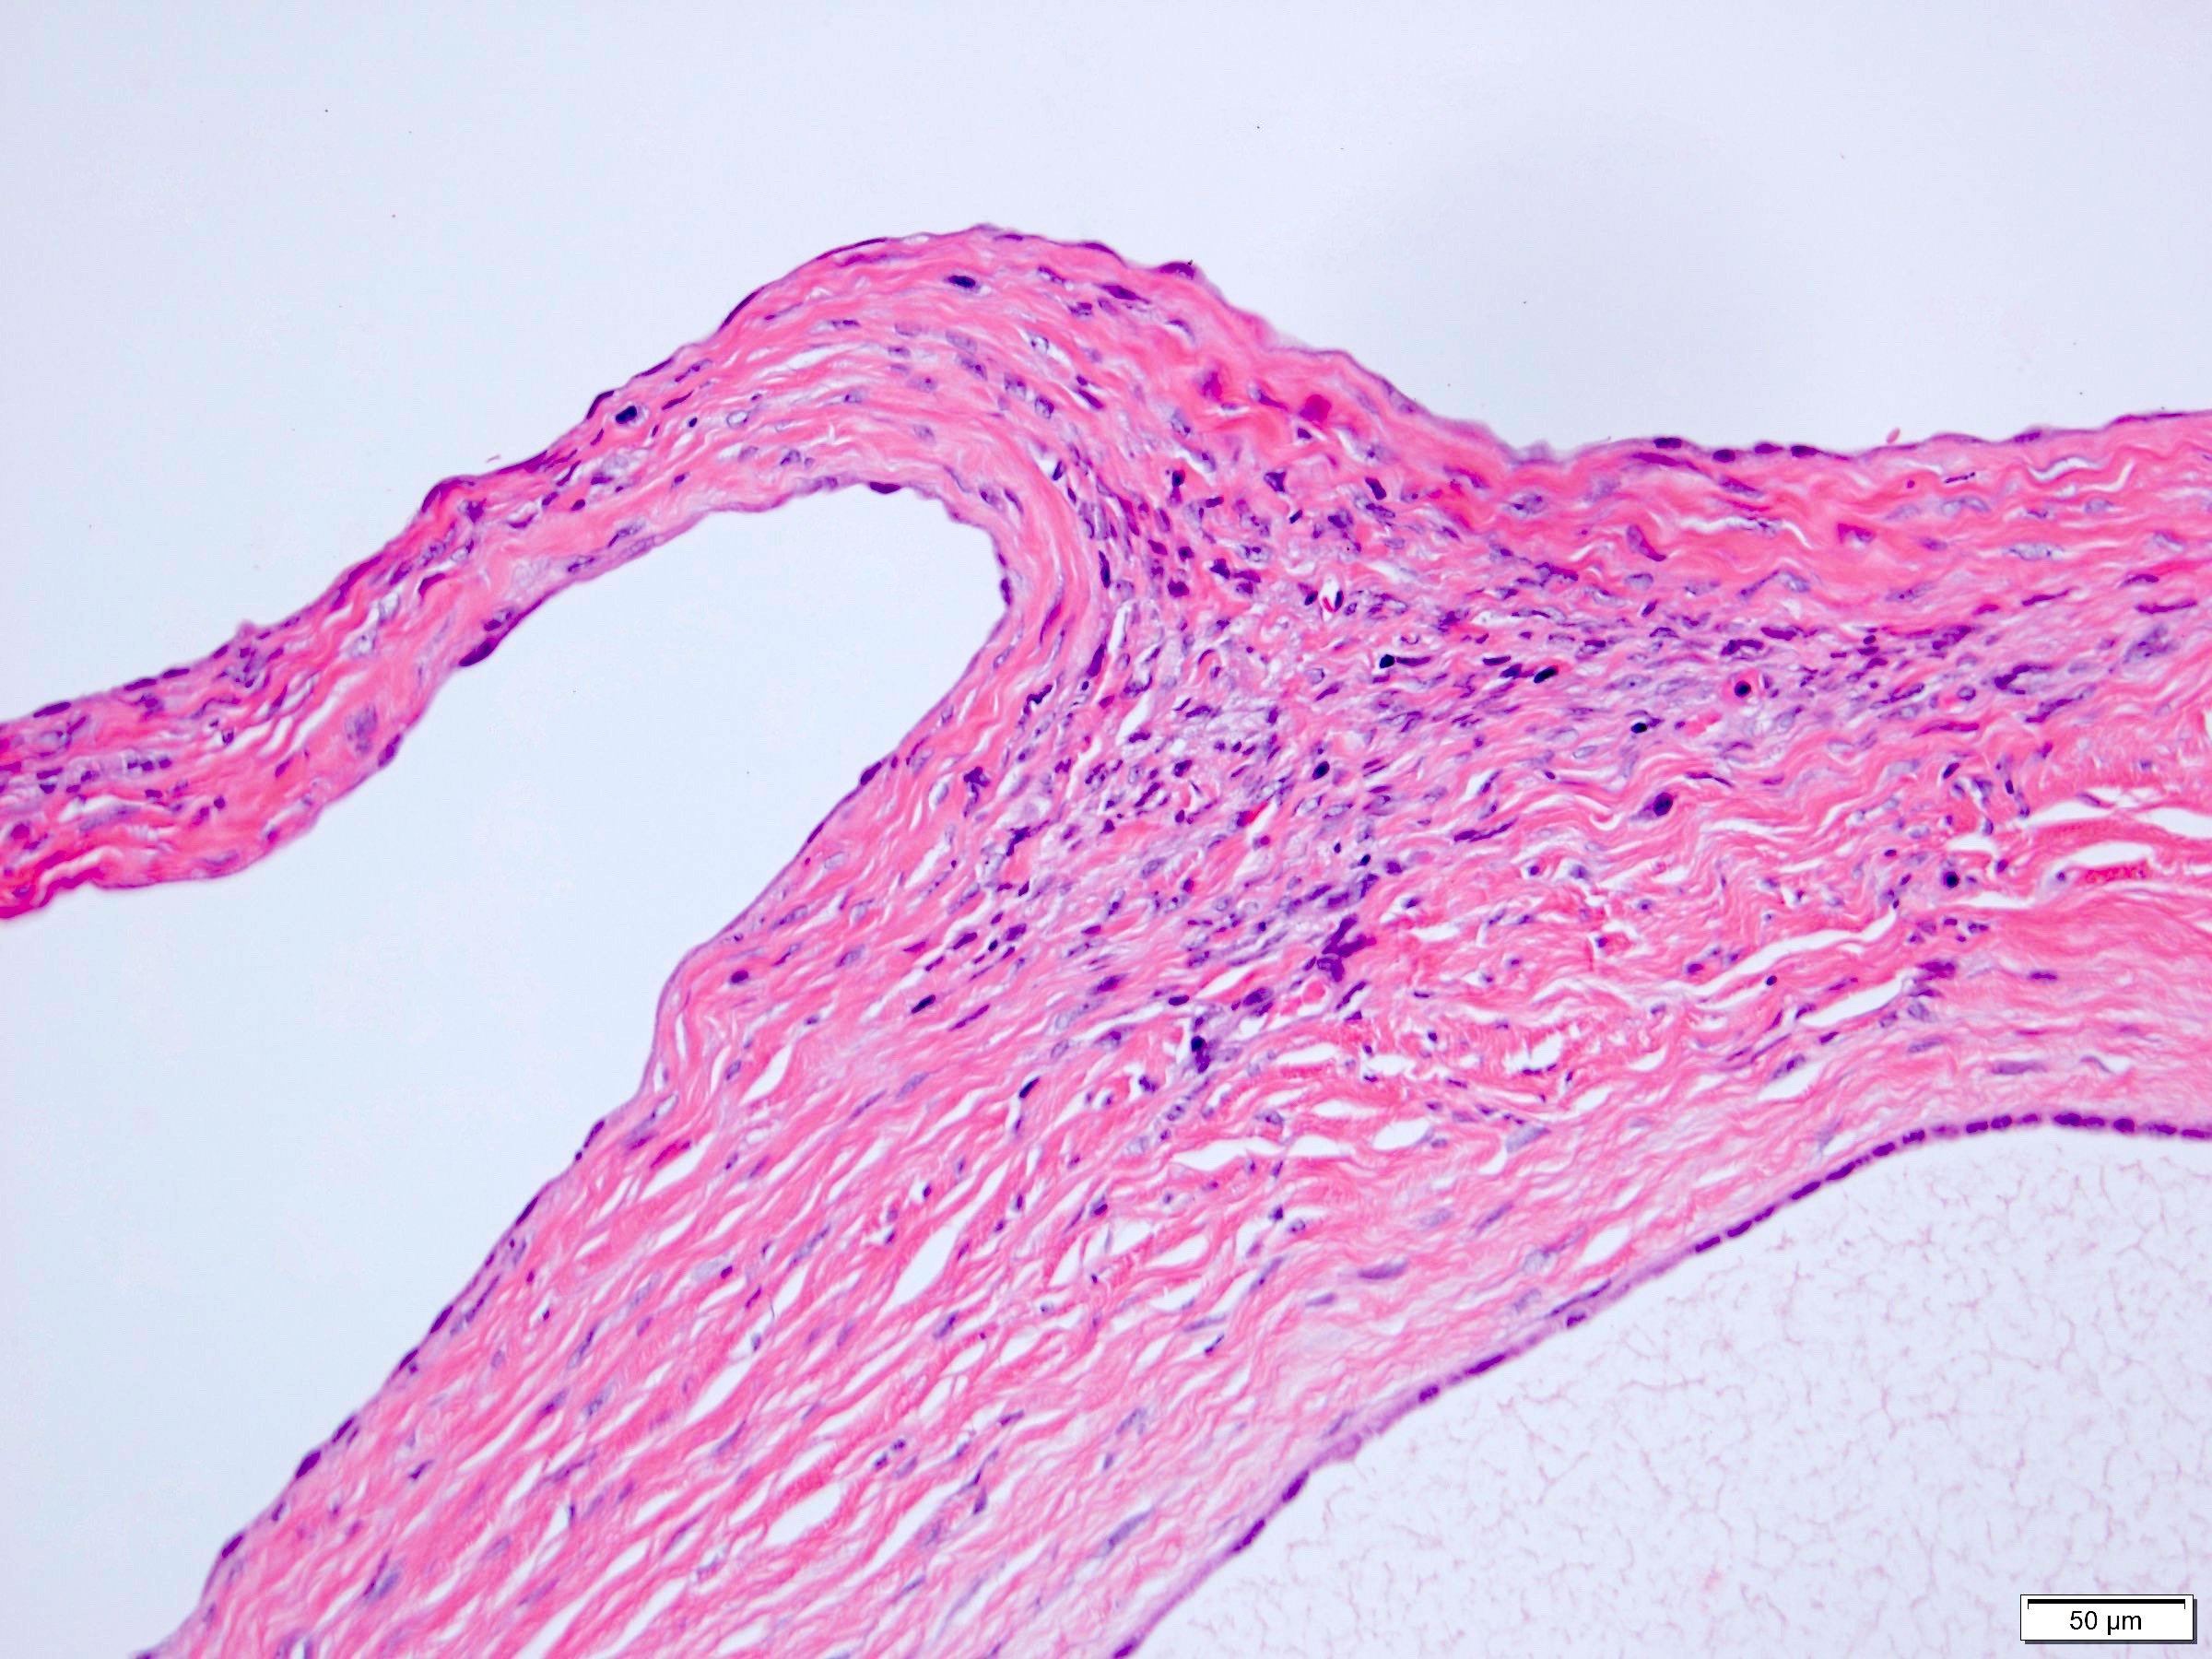

Microscopic (histologic) description

- Many with at least a partial pseudocapsule

- Entirely composed of cysts separated by septa (Semin Diagn Pathol 1998;15:2, Arch Pathol Lab Med 2004;128:1404, Am J Surg Pathol 2007;31:489, Eur Urol 2008;54:1237, Am J Surg Pathol 2016;40:1591)

- Stroma:

- Hypocellular to hypercellular

- Collagenous and fibrous to edematous and myxoid

Microscopic (histologic) images